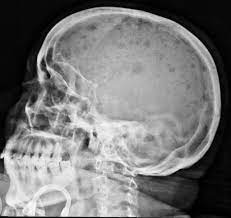

Multiple myeloma is a cancer of plasma cells, which are white blood cells found mainly in the bone marrow. Find more information on clinical trials that are open for enrollment at mount sinai's center for excellence for multiple myeloma. Multiple myeloma (mm), also known as plasma cell myeloma and simply myeloma, is a cancer of plasma cells, a type of white blood cell that normally produces antibodies. Treatment response, detection of relapse. Related online courses on physioplus. 16,000 new cases and 11,000 deaths. Changing the treatment landscape for hematologic malignancies learn more. In multiple myeloma, when the cancer protein level is up, the normal antibody levels are down. If you still can't find it, please let us know so we can add it!. Tell the radiologist or the radiology technician about your diagnosis before receiving dye injection into. It accounts for approximately 10% of all. Other tests include blood monoclonal immunoglobulin and radiology tests to determine the extent of bone lesions. Spotlight revised international staging system for multiple myeloma:

Multiple myeloma is a monoclonal gammopathy and is the most common primary malignant bone neoplasm in adults. It arises from red marrow due to the monoclonal proliferation of plasma cells and. Healthy plasma cells help you fight infections by making antibodies that recognize and attack germs. Multiple myeloma (mm), also known as plasma cell myeloma and simply myeloma, is a cancer of plasma cells, a type of white blood cell that normally produces antibodies. A report from international myeloma.